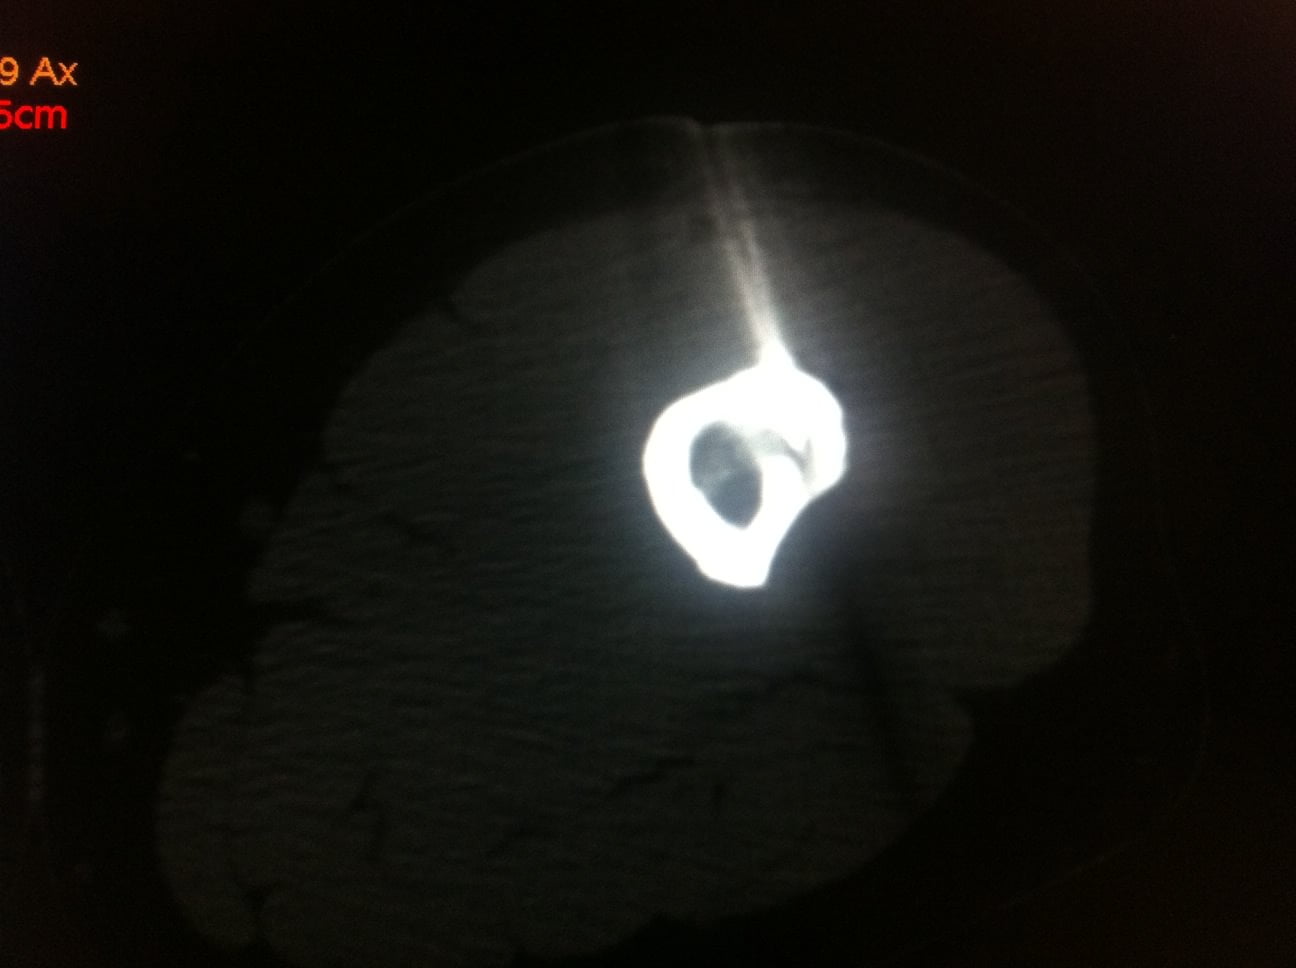

Sous guidage scopique et scanner un trocart 11 gauges coaxial Thiebaud t’AM est introduit dans la tumeur. Le contrôle itératif par scanner permet de positionner au plus près le matériel. Cette technique évite une ouverture cutanée mais surtout permet de conserver la structure osseuse adjacente et s’assure d’une précision optimale.

Nous réalisons la Mise en place d’une sonde de RF de 1mm au centre du nidus puis Ablation par RF à 90° pendant 4 à 5 mn